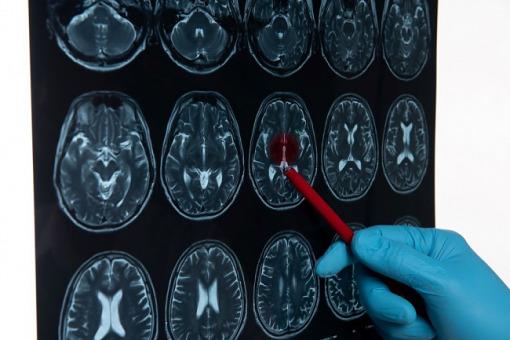

Program leczenia ostrej fazy udaru niedokrwiennego za pomocą przezcewnikowej trombektomii mechanicznej naczyń domózgowych lub wewnątrzczaszkowych nadal będzie funkcjonował w formule pilotażu.

Ministerstwo Zdrowia znowelizowało rozporządzenie dotyczące leczenia ostrej fazy udaru niedokrwiennego za pomocą przezcewnikowej trombektomii mechanicznej naczyń domózgowych lub wewnątrzczaszkowych i skierowało je do opiniowania.